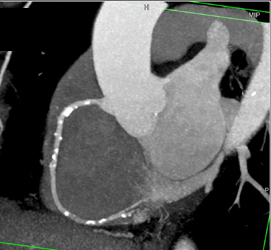

Diagnosis

Dissection Repair